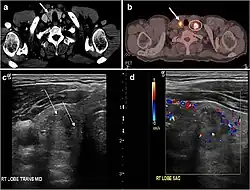

Fig. 7. A 51-year-old female patient post total thyroidectomy for PTC with elevated thyroglobulin measurement. an Axial non-enhanced CT scan of the neck at the level of the thyroid bed demonstrates a well-defined, rounded, homogenously dense soft tissue situated between the trachea and left internal jugular vein (white arrow). b Transverse ultrasound image of the neck demonstrates a well-defined, homogeneous, hypoechoic soft tissue nodule measuring 6 mm (white arrow) with no detected micro-calcifications. Biopsy showed a predominantly residual normal thyroid tissue with micro-foci of PTC.[1] -

Fig. 8. A 48-year-old male patient post total thyroidectomy with PTC recurrence. a Transverse greyscale ultrasound of the neck demonstrates a left thyroid bed heterogeneous, predominantly hypoechoic irregular lesion with calcifications (white arrow). b A spot image of iodine 123 total body scan of the neck demonstrate a focus of abnormal radiotracer uptake at the left thyroid bed (Black arrows) between the annotated markers. c Enhanced axial CT scan of the neck demonstrates an enhancing large left thyroid bed mass (white arrow) with no calcifications. The lesion exerts a mass effect on the oesophagus (black arrow) and is inseparable from the trachea.[1] -

Fig. 9. A 58-year-old male patient with persistence PTC at thyroid bed with hypervascular nodal metastasis. a–c Transverse greyscale and colour Doppler neck ultrasound demonstrate hypoehoic soft tissue in the left thyroid bed (white arrow in a). There are a heterogeneous enlarged lymph nodes at level 2 and 3 with markedly increased vascularity (white arrow in b and c). d–f Enhanced axial CT images of the neck demonstrate a 2.7 × 1.4 cm hypodense soft tissue lesion anterior to the left carotid sheath (white arrow). There are left-sided enhancing abnormal and enlarged lymph nodes at cervical level 2 and 3 (black arrows).[1]